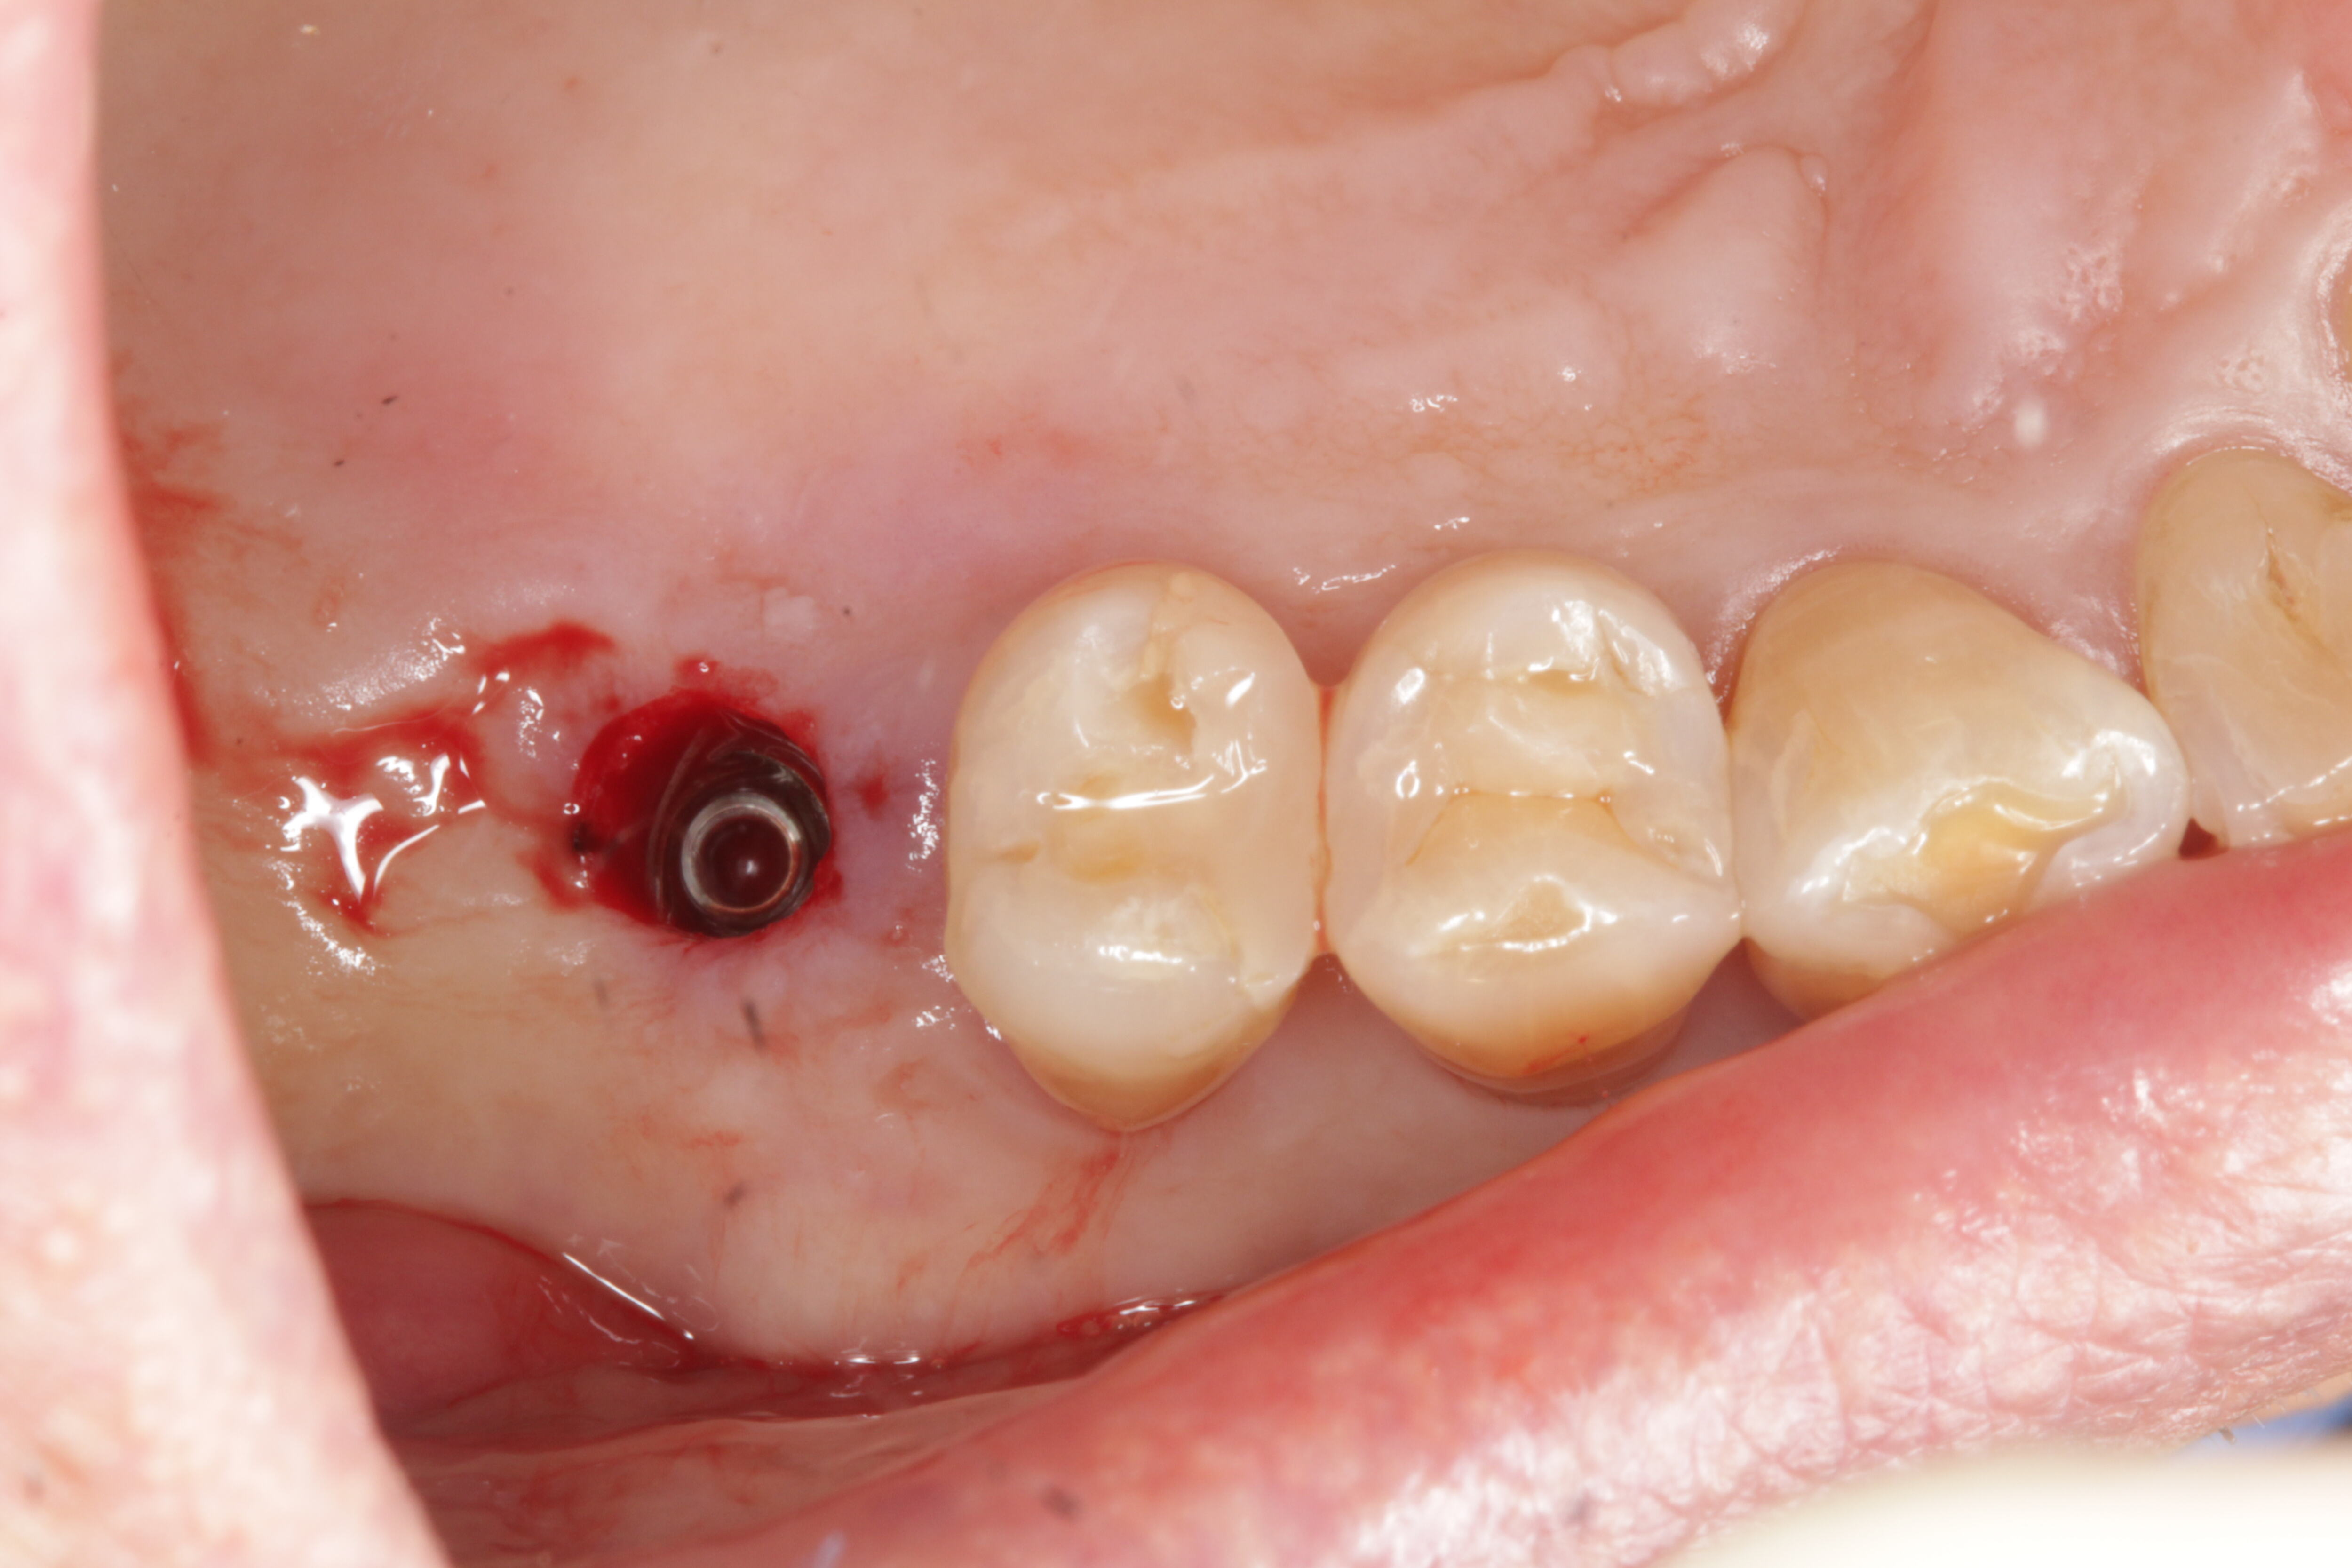

⋅ Guided Surgery

⋅ Guided Surgery

Guided Surgery Case 1

Guided Surgery Case 1